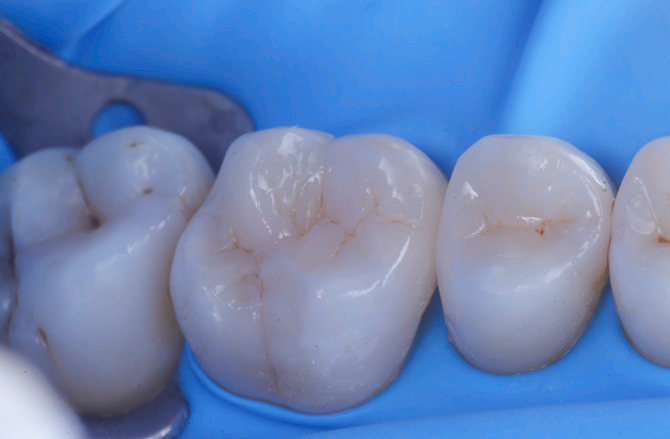

Fig.1 Fotografia inizialeFig.2 Isolamento e aspetto delle cavità ultimate

1

2